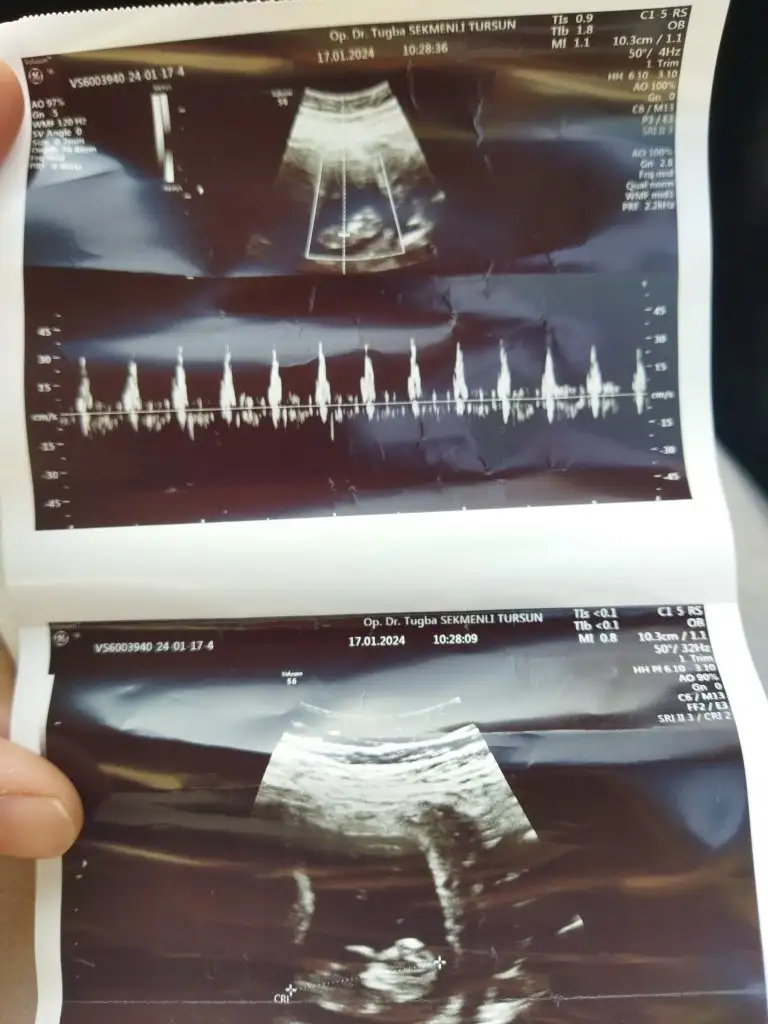

Merhaba, nub teorisine göre uzmanlardan cinsiyet tahmini rica etsem :) 11 haftalık

Aşağıda ilk resim benim bebiş, ikinci resimde teoriye göre baktım %70 kız gibi ama nub hafif yukarıda ve ucu birleşik değil.